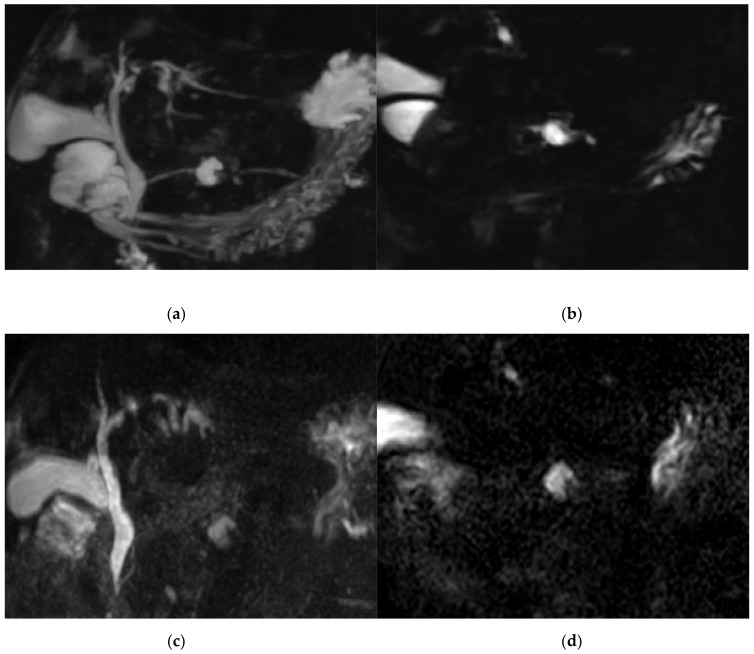

The score for image quality degradation by artifacts was significantly higher with BH-GRASE-MRCP than BH-CS-MRCP (4.86 ± 0.26 vs. 4.71 ± 0.42, p = 0.025). Background suppression, visualization of right and left 2nd level IHD, mid PD, and distal PD were significantly higher with BH-CS-MRCP than BH-GRASE-MRCP (p < 0.05, Table 2, Figure 2). However, overall image quality (p = 0.797), duct visualization of the CBD (p = 0.242), right (p = 0.589) and left 1st level IHD (p = 0.238), cystic duct (p = 0.089), and proximal PD (p = 0.643) did not show a significant difference between the imaging modalities (Figure 3). There were 24 patients with BD-IPMN who were considered to have communication between a cyst and the PD, while 21 patients (87.5%) on BH-CS-MRCP and 15 patients (62.5%) on BH-GRASE-MRCP demonstrated the presence of such communication (p = 0.07, Table 2, Figure 4).

A research associate (2 years of experience) provided the quantitative imaging analysis of the source images (two times over a 4-week interval). The mean values were used for the analysis. Using an approach like described in other previous studies, three representative slices (upper, middle, and lower CBD) depicting the center of the CBD for each patient were determined, and regions of interest (ROIs) were used to measure the signal intensity (SI) of the CBD and periductal tissues. ROIs for the SI of bile of at least 5 mm2 were used in homogeneous and artifact-free regions of the CBD in the middle third of its course. ROIs for the SI of periductal tissue and liver of at least 20 mm2 were placed in homogeneous and artifact-free regions adjacent to the ROI of the CBD [ref. 24,ref. 25]. Since the background noise was low, image noise was defined as the standard deviation (SD) of the CBD, periductal tissue, and the liver from the same ROIs as those used for SI measurements (Figure 1). The following formulae were used to evaluate the signal-to-noise ratio (SNR) of the CBD and the contrast ratio between the CBD and periductal tissues on 3D MRCP: